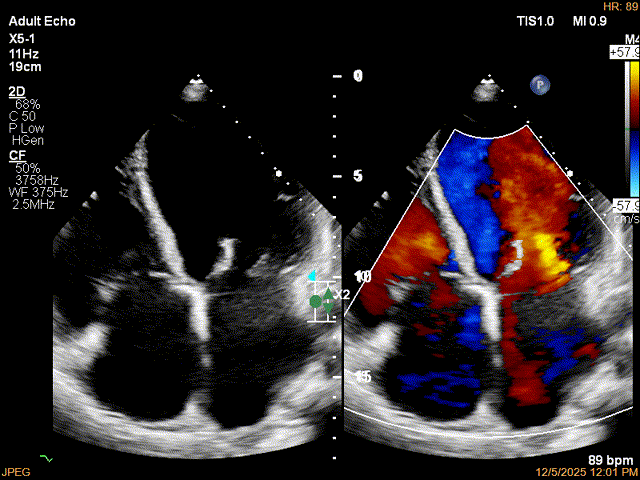

术后影像

最终结果3D-Zoom-color显示组织桥稳定,原脱垂区域前后叶对合部分的脱垂已消除,反流降至1+以下

夹子释放Bi-com切面显示残余反流情况

肺静脉收缩期逆流消失,频谱形态基本恢复正常

术后2D TTE:

术后TTE可见二尖瓣微量-轻度反流,三尖瓣反流明显改善降至中度